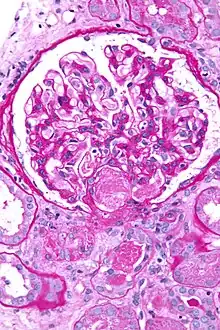

| Micrograph showing acute thrombotic microangiopathy due to DIC in a kidney biopsy. A clot is present in the hilum of the glomerulus (center of image). | |